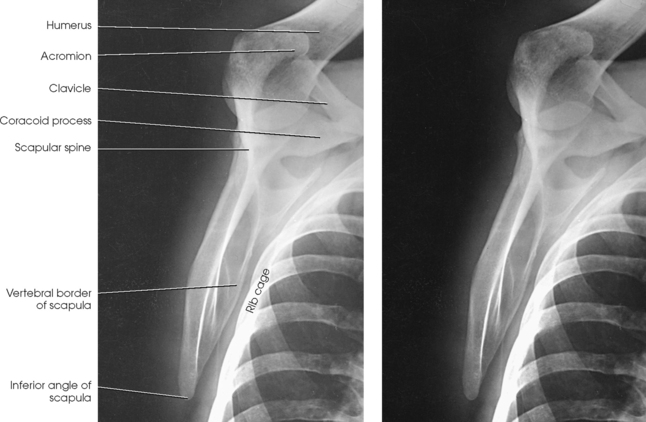

Structures shown: The image shows the bony and soft structures of the shoulder and proximal humerus in the anatomic position (Figs. 5-14 to 5-16). The scapulohumeral joint relationship is seen.

Fig. 5-14 A, AP shoulder, external rotation humerus: greater tubercle in profile (arrow). B, AP shoulder, neutral rotation humerus: greater tubercle (arrow).

Fig. 5-15 AP shoulder, internal rotation humerus: greater tubercle (arrow); lesser tubercle in profile (arrowhead).

Fig. 5-16 A, AP oblique projection of right shoulder without use of compensating filter. B, AP projection of same patient with compensating filter. Note improvement of visualization of bony and soft tissue areas with filter.

External rotation: The greater tubercle of the humerus and the site of insertion of the supraspinatus tendon are visualized (see Fig. 5-14, A).

Neutral rotation: The posterior part of the supraspinatus insertion, which sometimes profiles small calcific deposits not otherwise visualized (see Fig. 5-14, B), is seen.

Internal rotation: The proximal humerus is seen in a true lateral position. When the arm can be abducted enough to clear the lesser tubercle of the head of the scapula, a profile image of the site of the insertion of the subscapular tendon is seen (see Fig. 5-15).